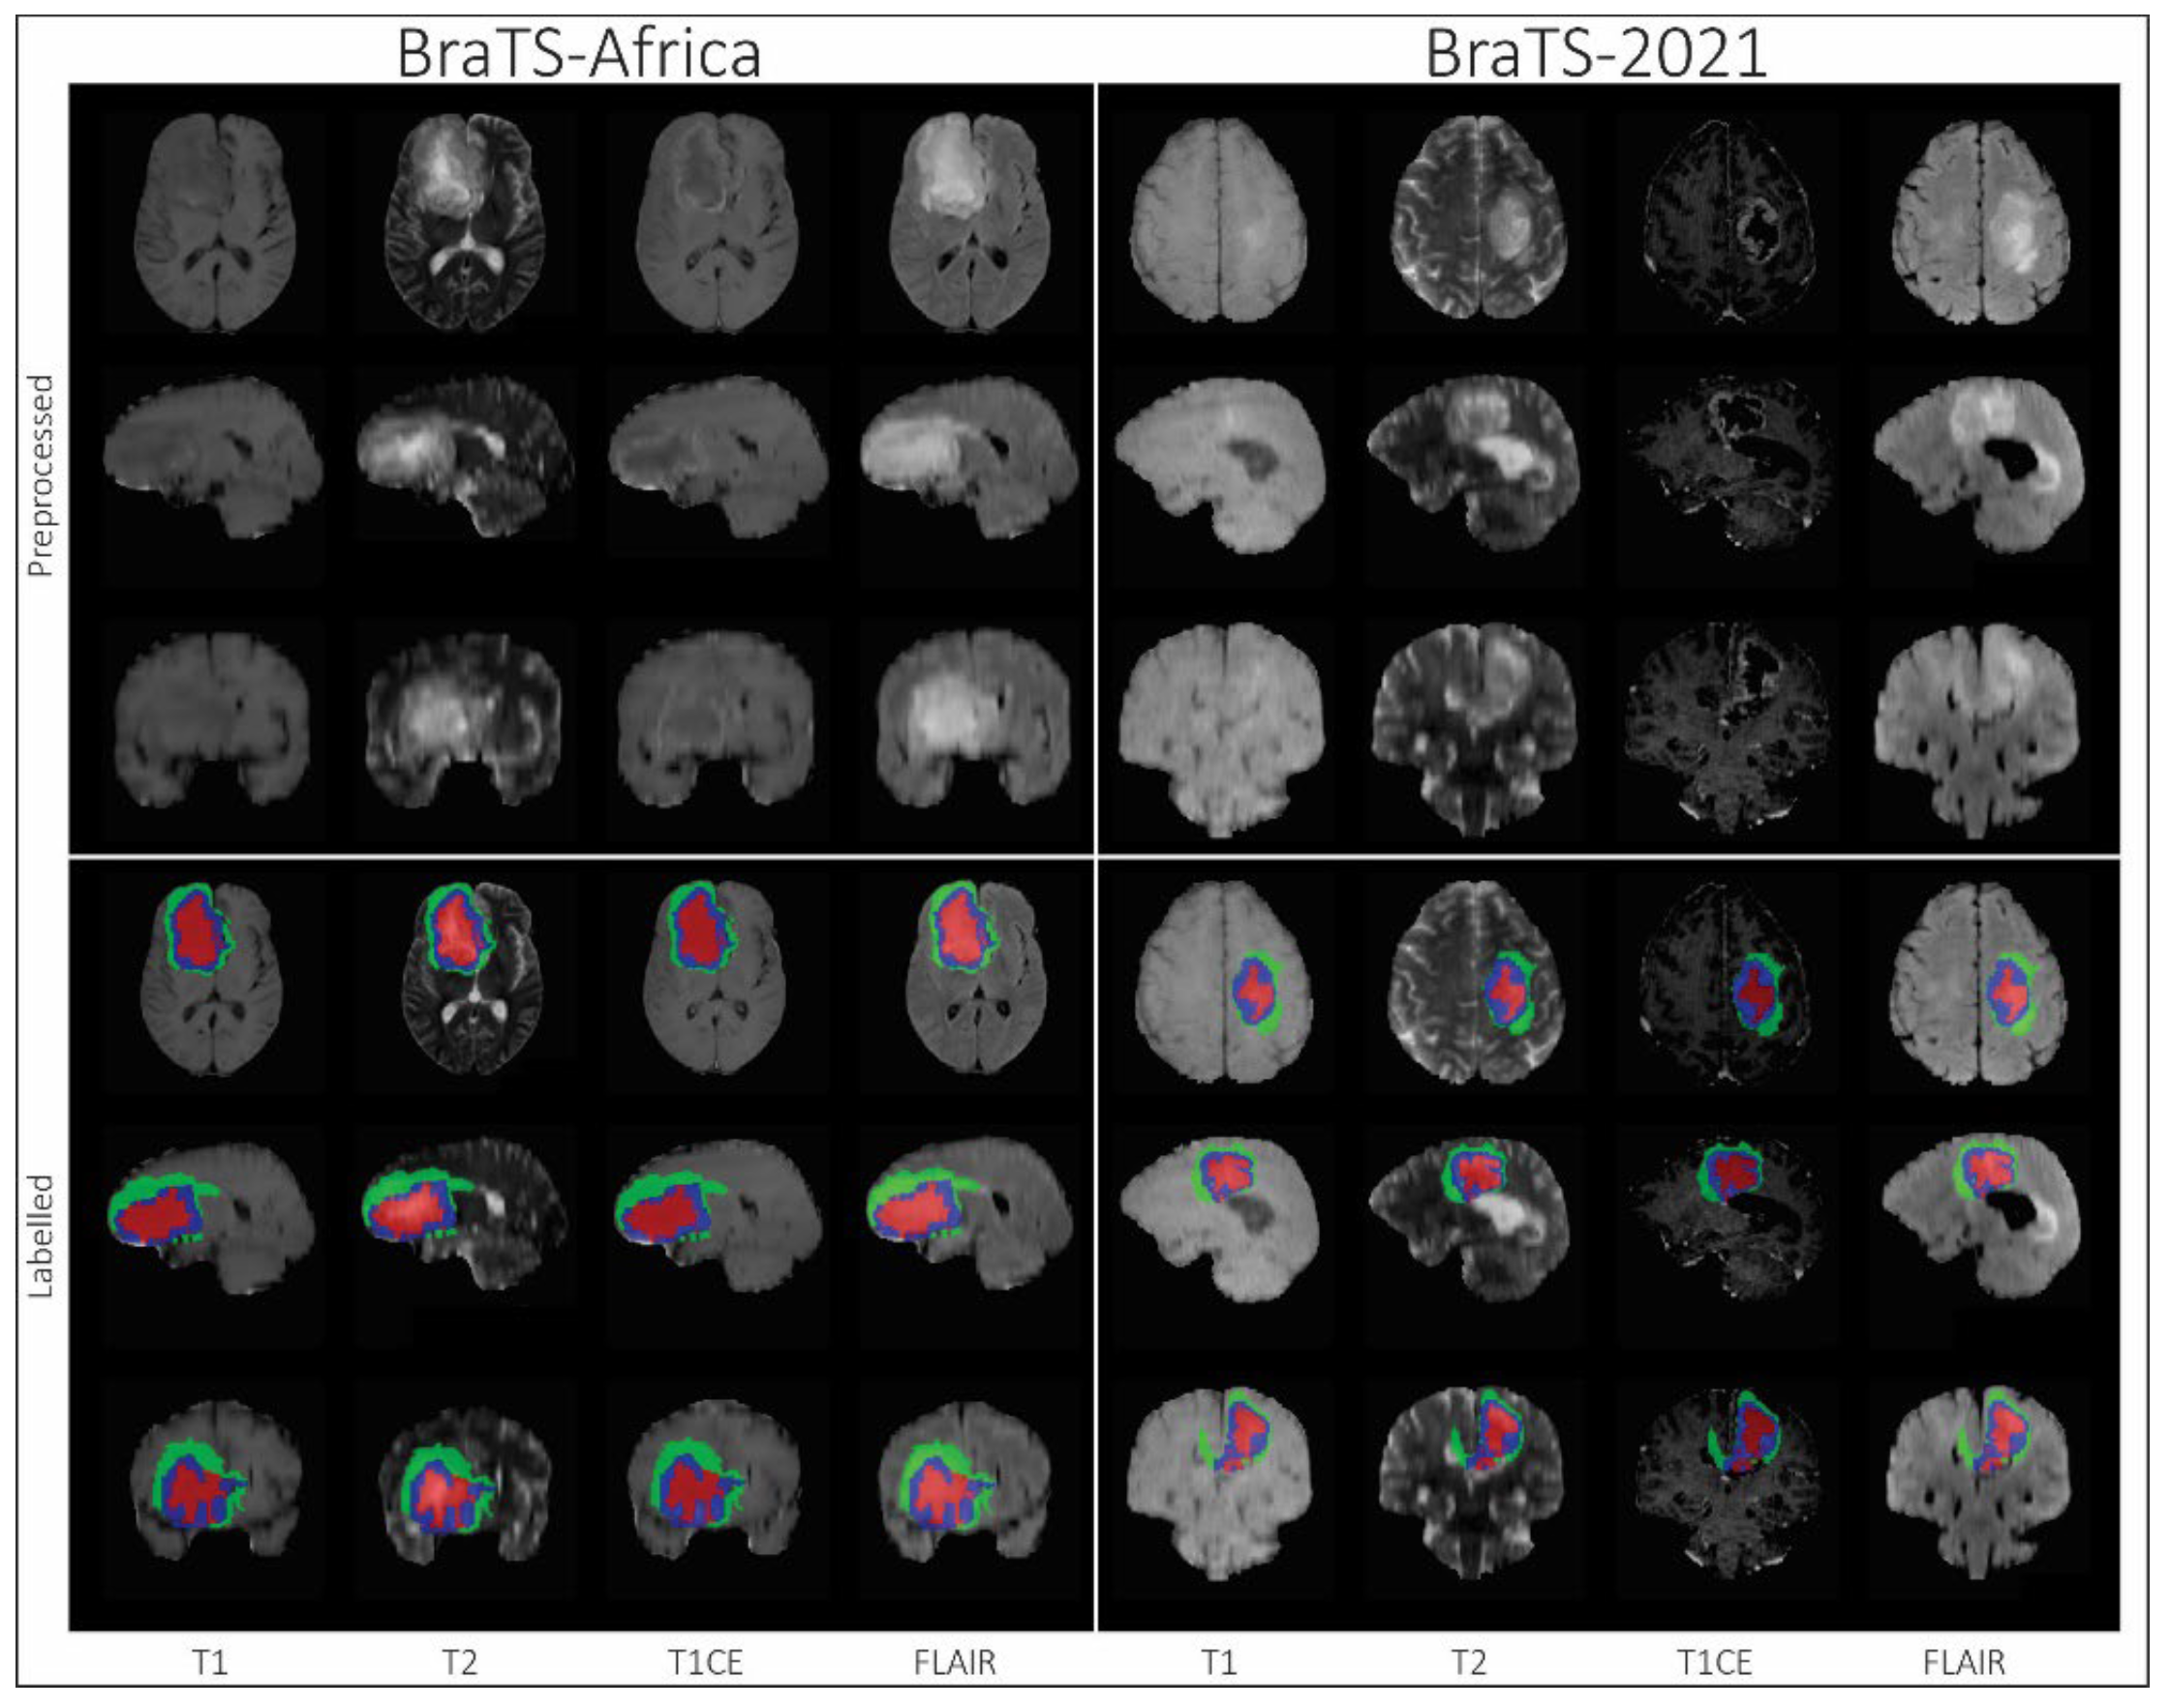

- Segmentation—BraTS-Africa: BraTS Challenge on Sub-Sahara-Africa Adult Glioma: The BraTS-Africa Challenge focuses on addressing the disparity in glioma treatment outcomes between high-income regions and Sub-Saharan Africa (SSA), where survival rates have not improved significantly due to factors such as the use of lower-quality MRI technology (see Figure 6), late-stage disease presentation, and unique glioma characteristics. Brain MRI scans from SSA typically exhibit reduced contrast and resolution, as demonstrated in Figure 6, which underscores the need for advanced pre-processing to enhance image quality prior to ML-based segmentation. This challenge is part of a broader effort to adapt and evaluate computer-aided diagnostic (CAD) tools for glioma detection in resource-limited settings, aiming to bridge the gap between research and clinical practice.The MICCAI-CAMERA-Lacuna Fund BraTS-Africa 2023 Challenge has assembled the largest publicly available retrospective cohort of pre-operative glioma MRI scans from adult Africans, including both low-grade glioma (LGG) and glioblastoma/high-grade glioma (GBM/HGG). The BraTS-Africa challenge involves developing machine learning algorithms to automatically segment intracranial gliomas into three distinct classes using a new 3-label system. The sub-regions for evaluation are enhancing tumor (ET), non-enhancing tumor core (NETC), and surrounding non-enhancing FLAIR hyperintensity (SNFH), which are crucial for enhancing diagnostic accuracy and treatment planning in these underserved populations [10,25].

- Segmentation—BraTS-Africa Dataset: All imaging data were reviewed and manually annotated by board-certified radiologists specializing in neuro-oncology, following the BraTS pre-processing and annotation protocols. Figure 9 demonstrates the new segmentation labeling introduced in 2023, which is also employed in the BraTS-Meningioma and BraTS-Metastasis 2023 challenge. This labeling system delineates three tumor sub-regions: